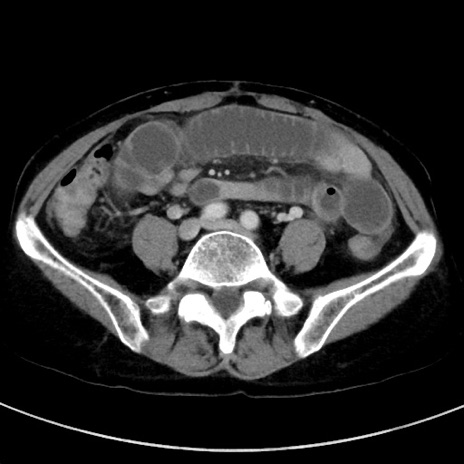

症例23(横断像)

【症例】70歳代女性

【主訴】下腹部痛・嘔吐

【現病歴】2日前より腹痛あり。昨日嘔吐あり。症状改善しないため来院。

【既往歴】胃GISTに対して胃部分切除後。

【身体所見】BT 37.1℃、BP 128/77mmHg、腹部:平坦・軟、下腹部に圧痛あり。

【データ】WBC 10200、CRP 0.31